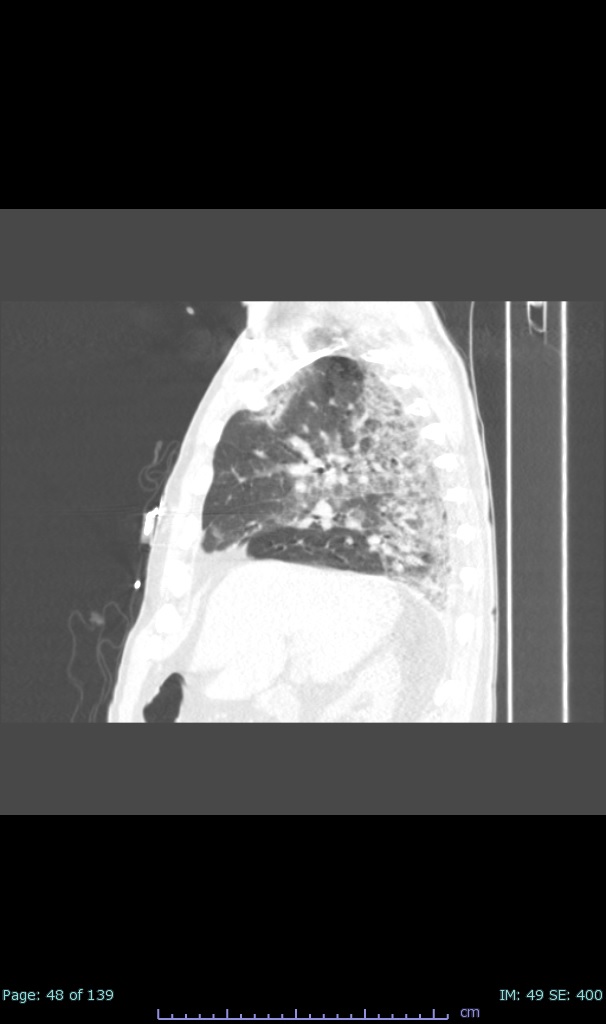

- 100% subpleural involvement, 33% + centrolobular involvement

- 40% even apical/basilar, 27% basilar dom, 5% mid dom. 1/17